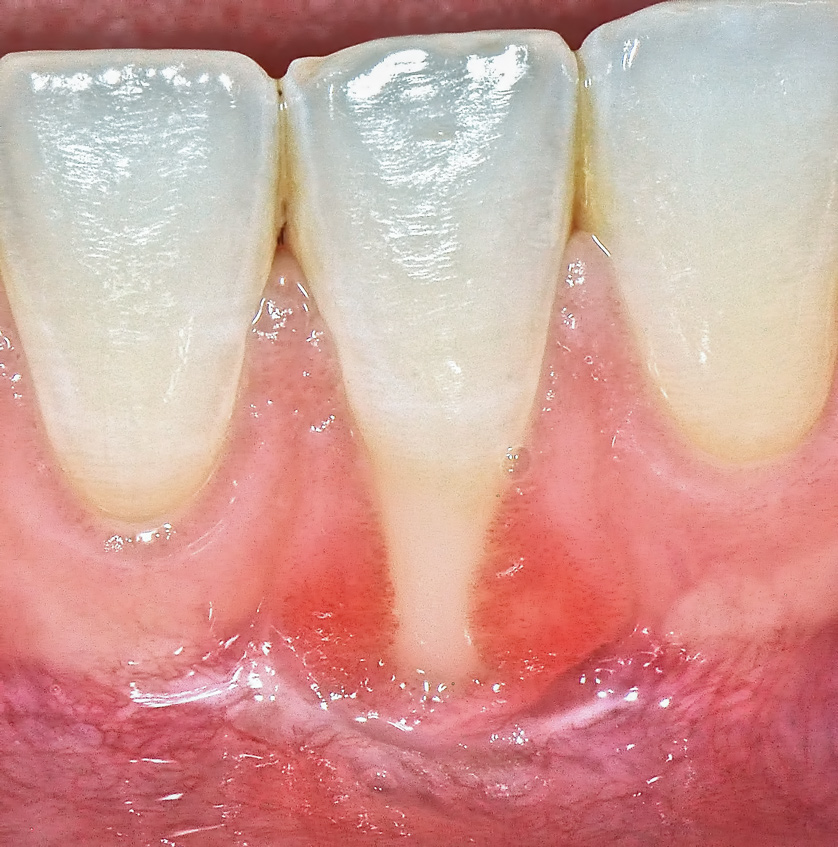

Although similar to the root coverage procedures mentioned above, gingival augmentation procedures not aimed at achieving root coverage are performed to facilitate plaque control, improve patient comfort, and prevent future periodontal recession. They may be used in conjunction with restorative, orthodontic, or prosthetic dentistry. The consensus report from the AAP's workshop group on soft-tissue non-root coverage procedures concluded that a specific minimum amount of keratinized tissue is not needed to prevent attachment loss when optimal plaque control is present; however, if plaque control is suboptimal, a minimum of 2 mm of keratinized tissue is needed. 12 A standard procedure that is recognized to predictably gain keratinized tissue is the use of an autogenous gingival graft.12 Figure 5 through Figure 8 demonstrate the healing progression of a patient with poor oral hygiene whose mucogingival defect was treated with a free gingival graft and L-PRF from the patient's own blood.

(5.) Pretreatment photo of patient with recession to be treated with a free gingival graft (harvested from the palate) and L-PRF.

Figure 5

(8.) Postoperative view of the graft recipient site after 6 months showing healing progress with poor oral hygiene.

Figure 8